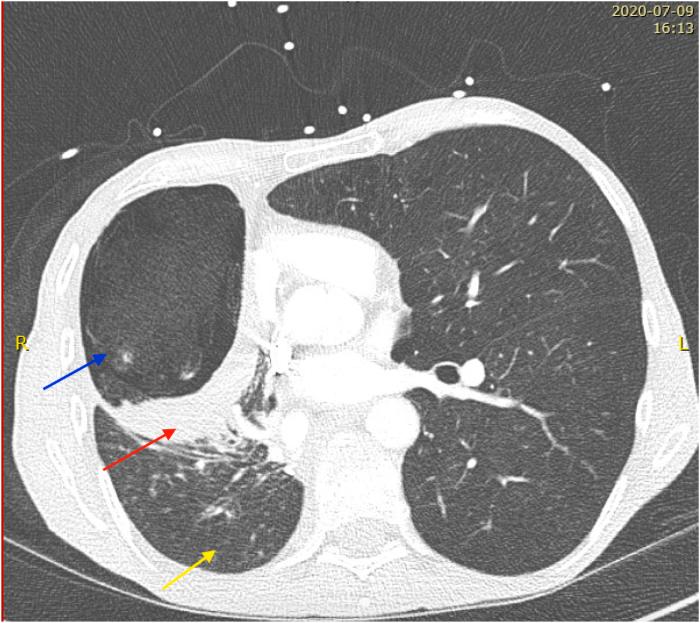

We present the case of a previously healthy 54-year-old man who was hospitalized for an Aspergillus fumigatus infection of an open window thoracotomy. Patient was successfully treated for 8 consecutives weeks with daily topical pleural liposomal amphotericine B administered by soaked gauzes combined with systemic therapy.

我们报告一例既往健康的54岁男性,因开放性胸廓切开术后烟曲霉感染入院。患者通过浸泡纱布每日局部应用脂质体两性霉素B并结合全身治疗,连续成功治疗8周。